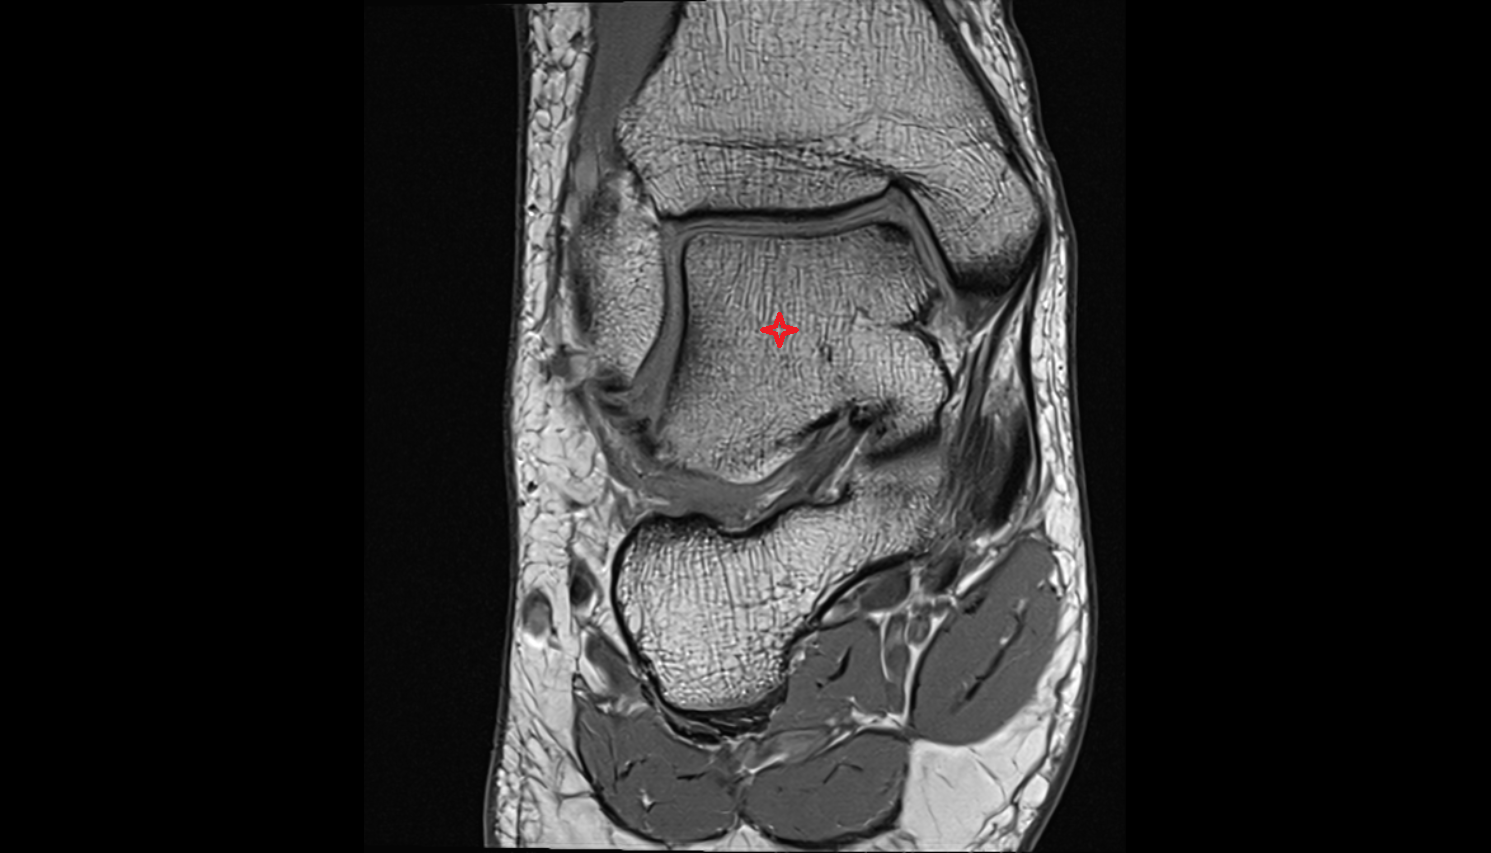

- Talus

- Head of talus

- Body of talus

- Neck of talus

- Calcaneus

- Sustentaculum tali

- Ankle joint

- Talocalcaneal joint

- Achilles tendon